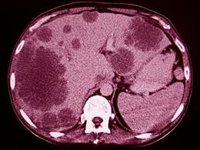

Los investigadores del Cedars-Sinai de Nueva York (Estados Unidos) han desarrollado un método para ayudar a identificar qué microbios del intestino humano tienen más probabilidades de contribuir a una serie de enfermedades inflamatorias como la obesidad, la enfermedad hepática, la enfermedad inflamatoria intestinal, el cáncer y algunas enfermedades neurológicas.

La técnica, descrita en la revista 'Science Translational Medicine', utiliza una proteína presente en la sangre que detecta los microbios intestinales que han cruzado la barrera intestinal y activado las células inmunitarias de todo el organismo, un avance que podría conducir a nuevos tratamientos dirigidos a los microbios intestinales inflamatorios.

Aunque se cree que el microbioma intestinal desempeña un papel importante en las enfermedades provocadas por la sobreactivación inmunitaria, muchas de estas enfermedades afectan a órganos más allá del intestino. En la actualidad, existen herramientas limitadas para identificar qué microbios intestinales han cruzado la barrera intestinal y activado las células inmunitarias fuera del tracto gastrointestinal.